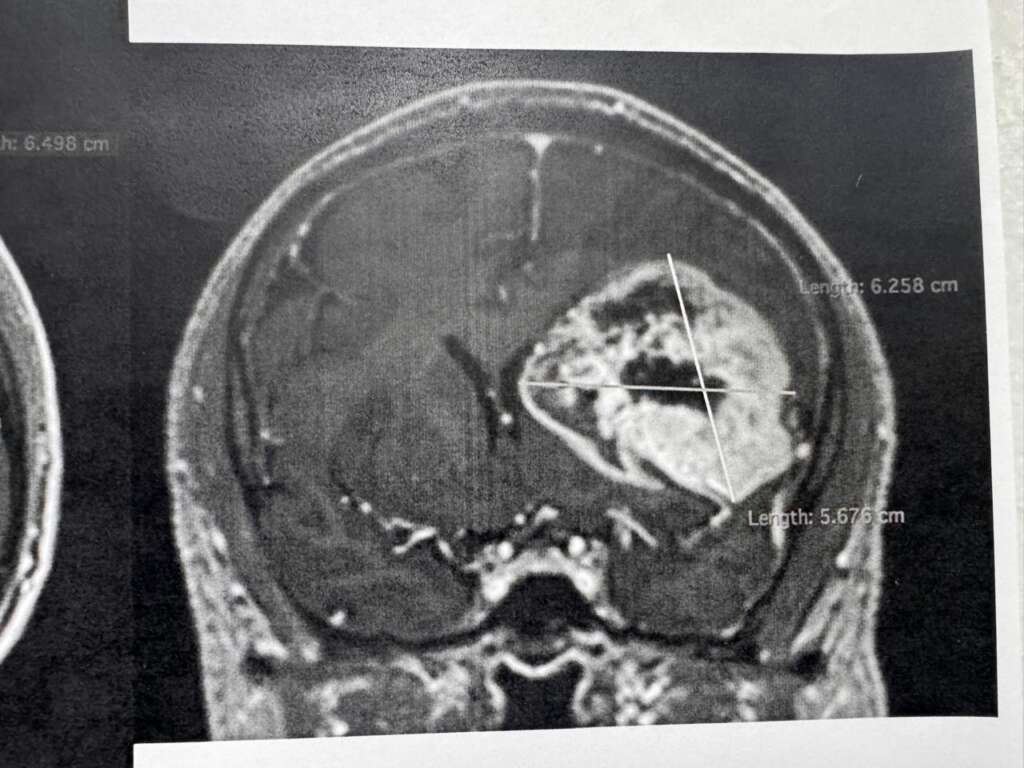

Para determinar la realización de este procedimiento y conocer el orígen de los síntomas, explicó, el equipo médico del Instituto le realizó al derechohabiente estudios de tomografía y resonancia magnética.

“Se realizó tomografía de cráneo y, ante los hallazgos, se le practicó una resonancia magnética; posteriormente, se le detectó un tumor de características malignas en la región frontal premotora izquierda”, detalló.